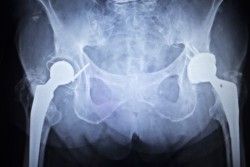

metal-hip-lawsuitA Georgia couple recently filed a lawsuit against Biomet, Inc., alleging that the company’s artificial hip implant was defective and harmful.

Plaintiff Dana B. was implanted with a Biomet M2a Magnum artificial hip device on August 30, 2011, to help with her degenerative joint disease.

On March 20, 2012, Dana underwent a second artificial hip implant surgery, this time for her other hip. A M2a magnum artificial hip device was used once again. This second surgery seemed to go well, and no complications were discernible in the immediate aftermath of the surgery.